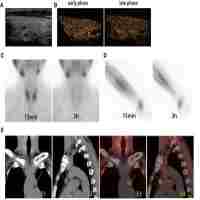

| Abstract | Background. Parathyroidectomy (PTx) is the most successful treatment for advanced secondary hyperparathyroidism (2HPT) not responsive to medical treatment. However, persistent HPT remains problematic after PTx if some glands remain. The clinical course in patients with persistent 2HPT was evaluated to clarify the risk for re‐operation after PTx. Methods. Between March 1981 and December 2001, initial total PTx with forearm autograft were performed in 1156 uraemic patients. Persistent HPT cases were defined as those in which the lowest post‐operative intact parathyroid hormone (i‐PTH) concentration was >60 pg/ml, and patients were classified into groups A, B and C, with i‐PTH concentrations of ≥500, 300–500 and 60–300 pg/ml, respectively. These patients were followed for 7–234 months after PTx. Results. Persistent HPT was identified in 49/1156 patients (4.2%), with nine cases in group A, 10 in group B and 30 in group C. Re‐operation was required in 21/49 (42.8%) cases, and in seven of these the last i‐PTH concentration was ≥500 pg/ml. All cases in group A required re‐operation. In group C, 11/30 (36.7%) patients required re‐operation. The missed glands removed at re‐operation were supernumerary in 14 cases, and located in the mediastinum in 13 cases. The frequency of advanced HPT and re‐operation was not negligible. Conclusions. To prevent persistent 2HPT, all parathyroid glands must be found and resected during the initial operation. Even if small parathyroid glands remain, there is a risk of progression. Complete PTx is the first treatment choice for advanced 2HPT. |